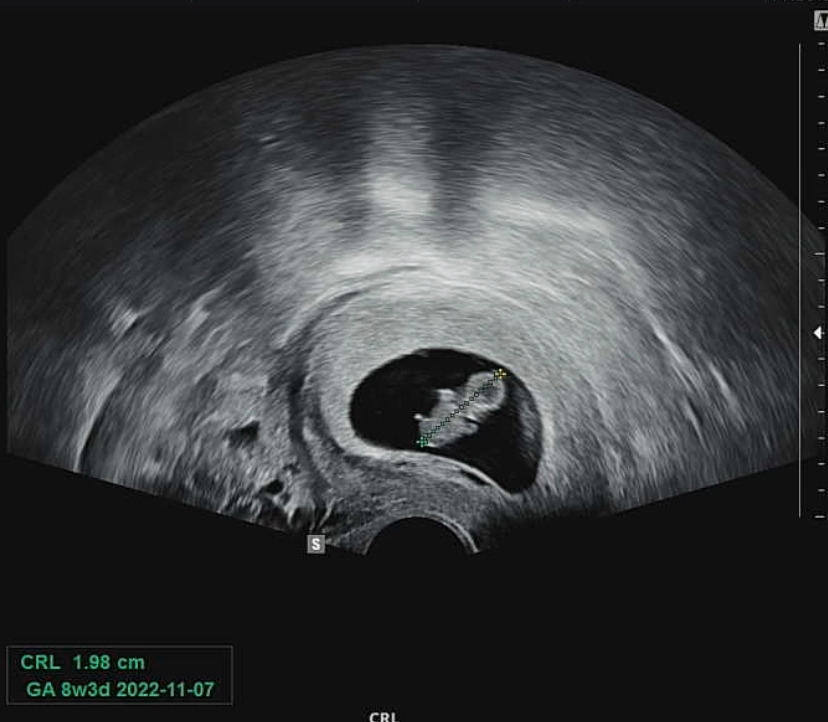

3월 31일 (8주 차 반) 2주 기다려서 초음파 보는 날~ 잘 크고 있나 너무 궁금했는데 8주 지났다고 팔다리도 뿅뿅 나고 완벽한 젤리 곰 형태를 띠고 있어서 너무 신기했다.

IMG_1217.jpg 신장 2cm 늠름하게 커진 젤리 곰 범이